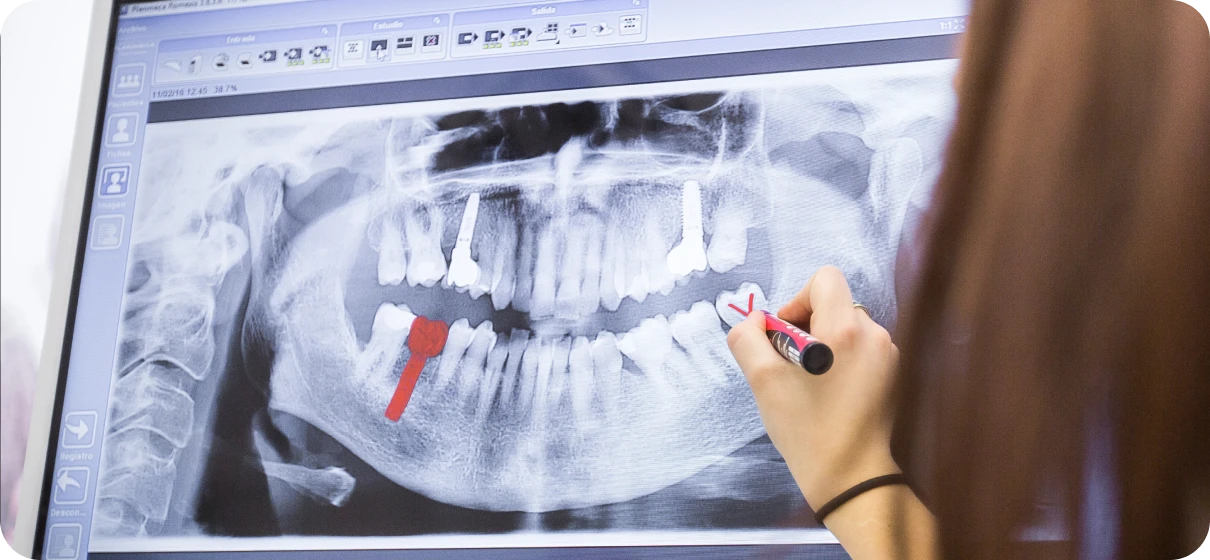

Radio 2D 3D

La radiographie numérique 2D et 3D est un outil diagnostique essentiel qui permet d'obtenir des images précises des dents, des os et des structures environnantes, offrant une vision complète pour un diagnostic fiable et un plan de traitement optimal.